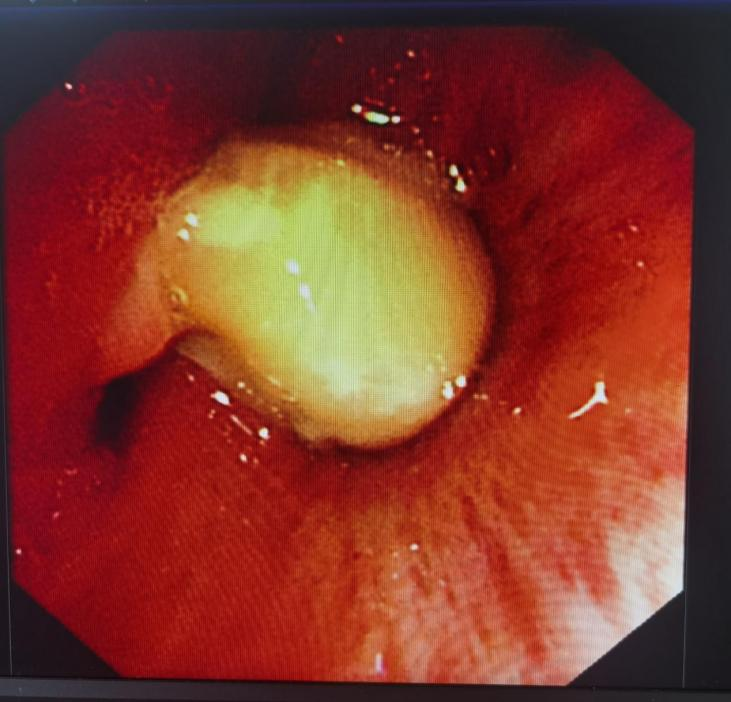

住院后立即给吴先生预约了气管镜检查,没多久,便顺利完成了全麻支气管镜检查。

检查过程中,在镜下右下支气管开口清晰地见到了异物,沈亚青主治医生娴熟精密地用活检钳及圈套器顺利将其取出。

术后吴先生长舒一口气,当即表示胸口舒服多了。